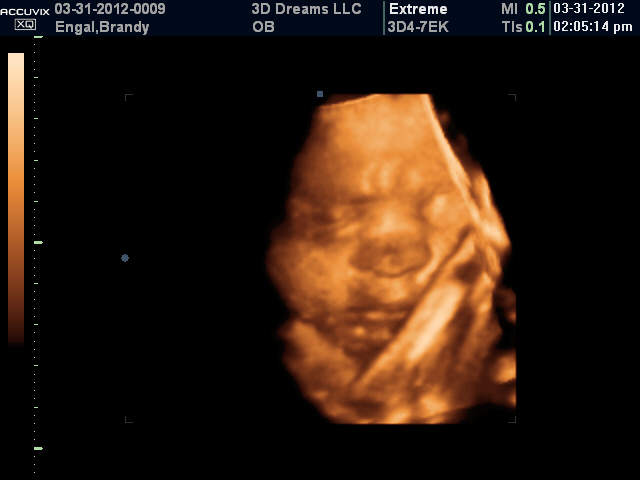

We had an amazing day seeing our baby girl for the first time at our 3D ultrasound.  It was amazing to be able to see all of her features.  We could distinctly see all her fingers and toes.  We even saw that she has a little bit of hair...hooray for hairbows!  3D Dreams did an also job and allowed us to view 3D and 4D images of our baby. The ultrasound tech kept saying "She has beautiful lips!"  Zoey really made us laugh by keeping one foot right beside her cheek.  She was in a split the whole time...I guess she'll be a cheerleader like mommy after all!  The tech said our baby girl would definitely be a snuggler...I know MiMi will eat that up! We were so glad that the soon to be grandparents were there to take part in the fun with us!

Pretty girl!